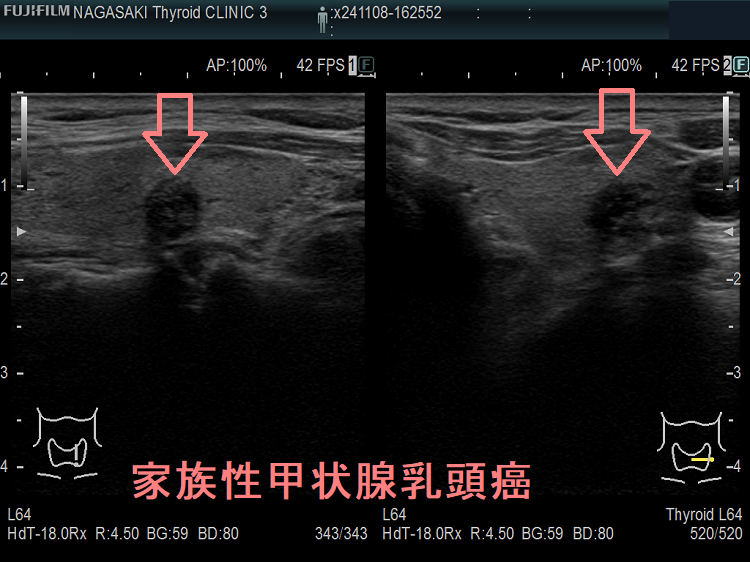

甲状腺癌の85%を占める甲状腺乳頭癌の5-8%は遺伝性であり、多くは常染色体優性遺伝と考えられています。第一度近親者に3名以上見つかれば家族性甲状腺乳頭癌とほぼ確定されます。血縁者内でBRAFという遺伝子の同じ個所に変異が証明できます。

近親者が甲状腺乳頭癌をされている方は、甲状腺超音波(エコー)検査が必要です。

また、御自分が甲状腺乳頭癌なら、血縁者の甲状腺超音波(エコー)検査が必要です。

家族性非髄様癌性甲状腺癌(FNMTC)は、おもに甲状腺乳頭癌で前述のことです(甲状腺濾胞癌もありますが)。遺伝形式は、不完全浸透の常染色体優性遺伝(要するに50%の確率で遺伝する)です。

患者本人と、第一度近親者(両親、兄弟姉妹、子供)に2名以上の非髄様性甲状腺がん(甲状腺乳頭癌・甲状腺濾胞癌)患者が存在し、かつ、明らかな症候群(表1の遺伝性甲状腺腫瘍)を伴わないものです。3名以上で95%以上、2名以上で50%遺伝性があります。